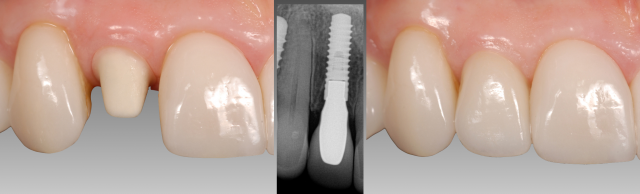

The definitive abutment chosen was a UCLA-metal ceramic abutment. The abutment was designed with ceramic added over the entirety of the surface (not just sub-gingival) so that an all-ceramic restoration (e.max) could be used for the crown. The benefit of the entire surface being baked with ceramic is that if desired, the abutment could be etched and silanated to allow the restoration to be bonded with resin cement. (Fig. 7)

Variations in the abutment design do exist. The decision to build the entire abutment with ceramic depends on the amount of space present. If required due to space limitations, the occlusal part of the abutment can either be opaqued only or left either as metal. (Fig. 8)